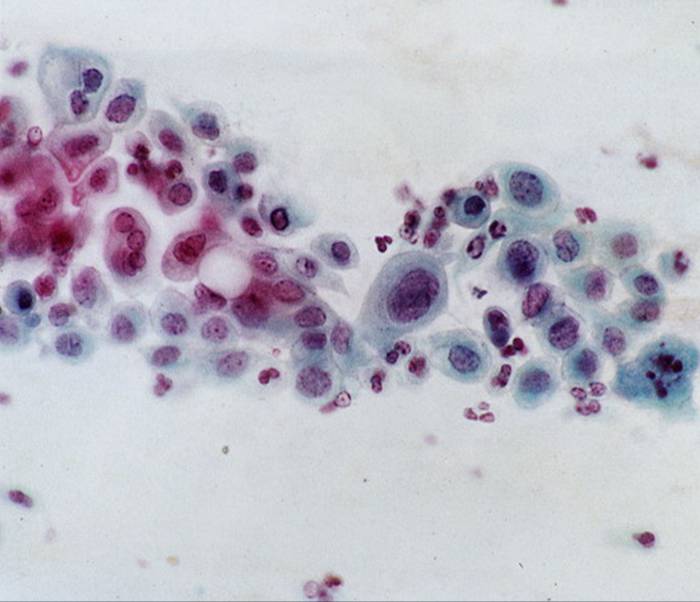

TBS-46.LSIL:低度鳞状上皮病变

TBS-47.LSIL(HPV)